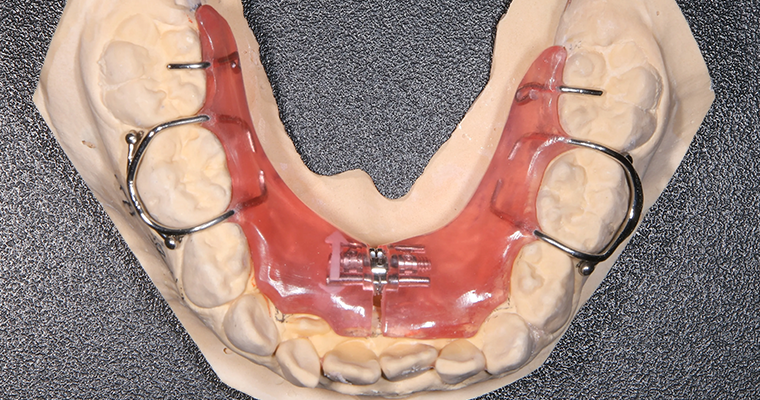

使用矯正装置 下

| 主訴 | 歯並びが悪い 乳歯と永久歯が重なっている 歯がまっすぐはえてこない |

|---|---|

| 治療期間 | 6-7ヶ月 |

| 治療費 | 440,000円(税込) ※調整、器具、治療後にお渡しするEFLine(矯正後の後戻りを防ぐ器具)も全て込みでの金額となっております。 |

| 治療内容 | 拡大床矯正 EF Lineで筋機能療法 |